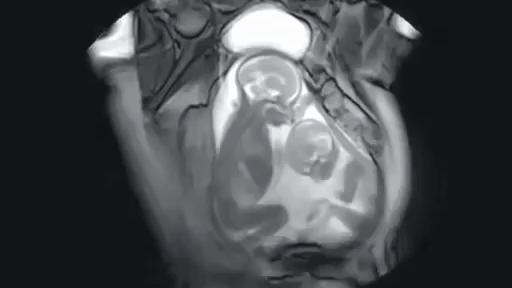

一名双胞胎孕妇的磁共振扫描。